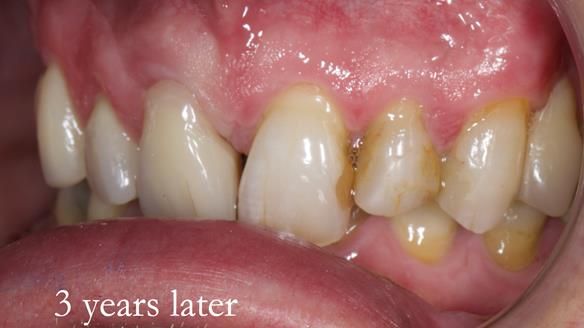

Treatment Process: I provided the clinical work, while Rowan Garstang handled the technical work. The treatment required five visits to fit the RPD. The worn lower anterior teeth were then built up. Unfortunately, I did not check the guidance on the denture teeth after this, and tooth 11 fractured off the denture. Brian was very understanding, and I adjusted the denture thoroughly. It has been fracture-resistant and trouble-free for the last three years.